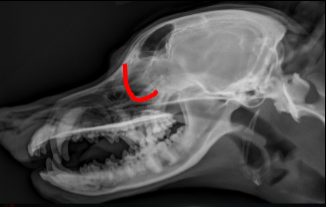

Temporomandibular Joint

ID radiographic view

VD